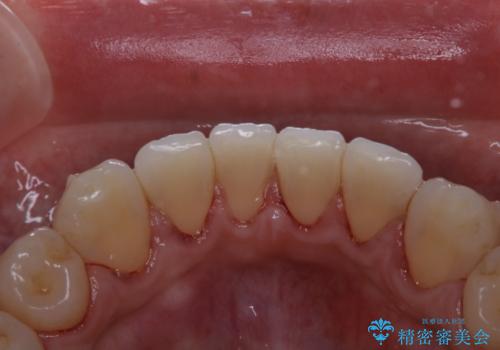

- インビザラインでのマウスピース矯正中の患者様です。

歯石による舌ざわりが気になるとのことでした。

PMTC30分コースを行いました。

PMTCは審美的な面だけではなく、虫歯や歯周病予防にもなります。

矯正治療中(ワイヤー・マウスピース共に)虫歯や歯周病予防のためには、お口の中を清潔に保つことが大切です。